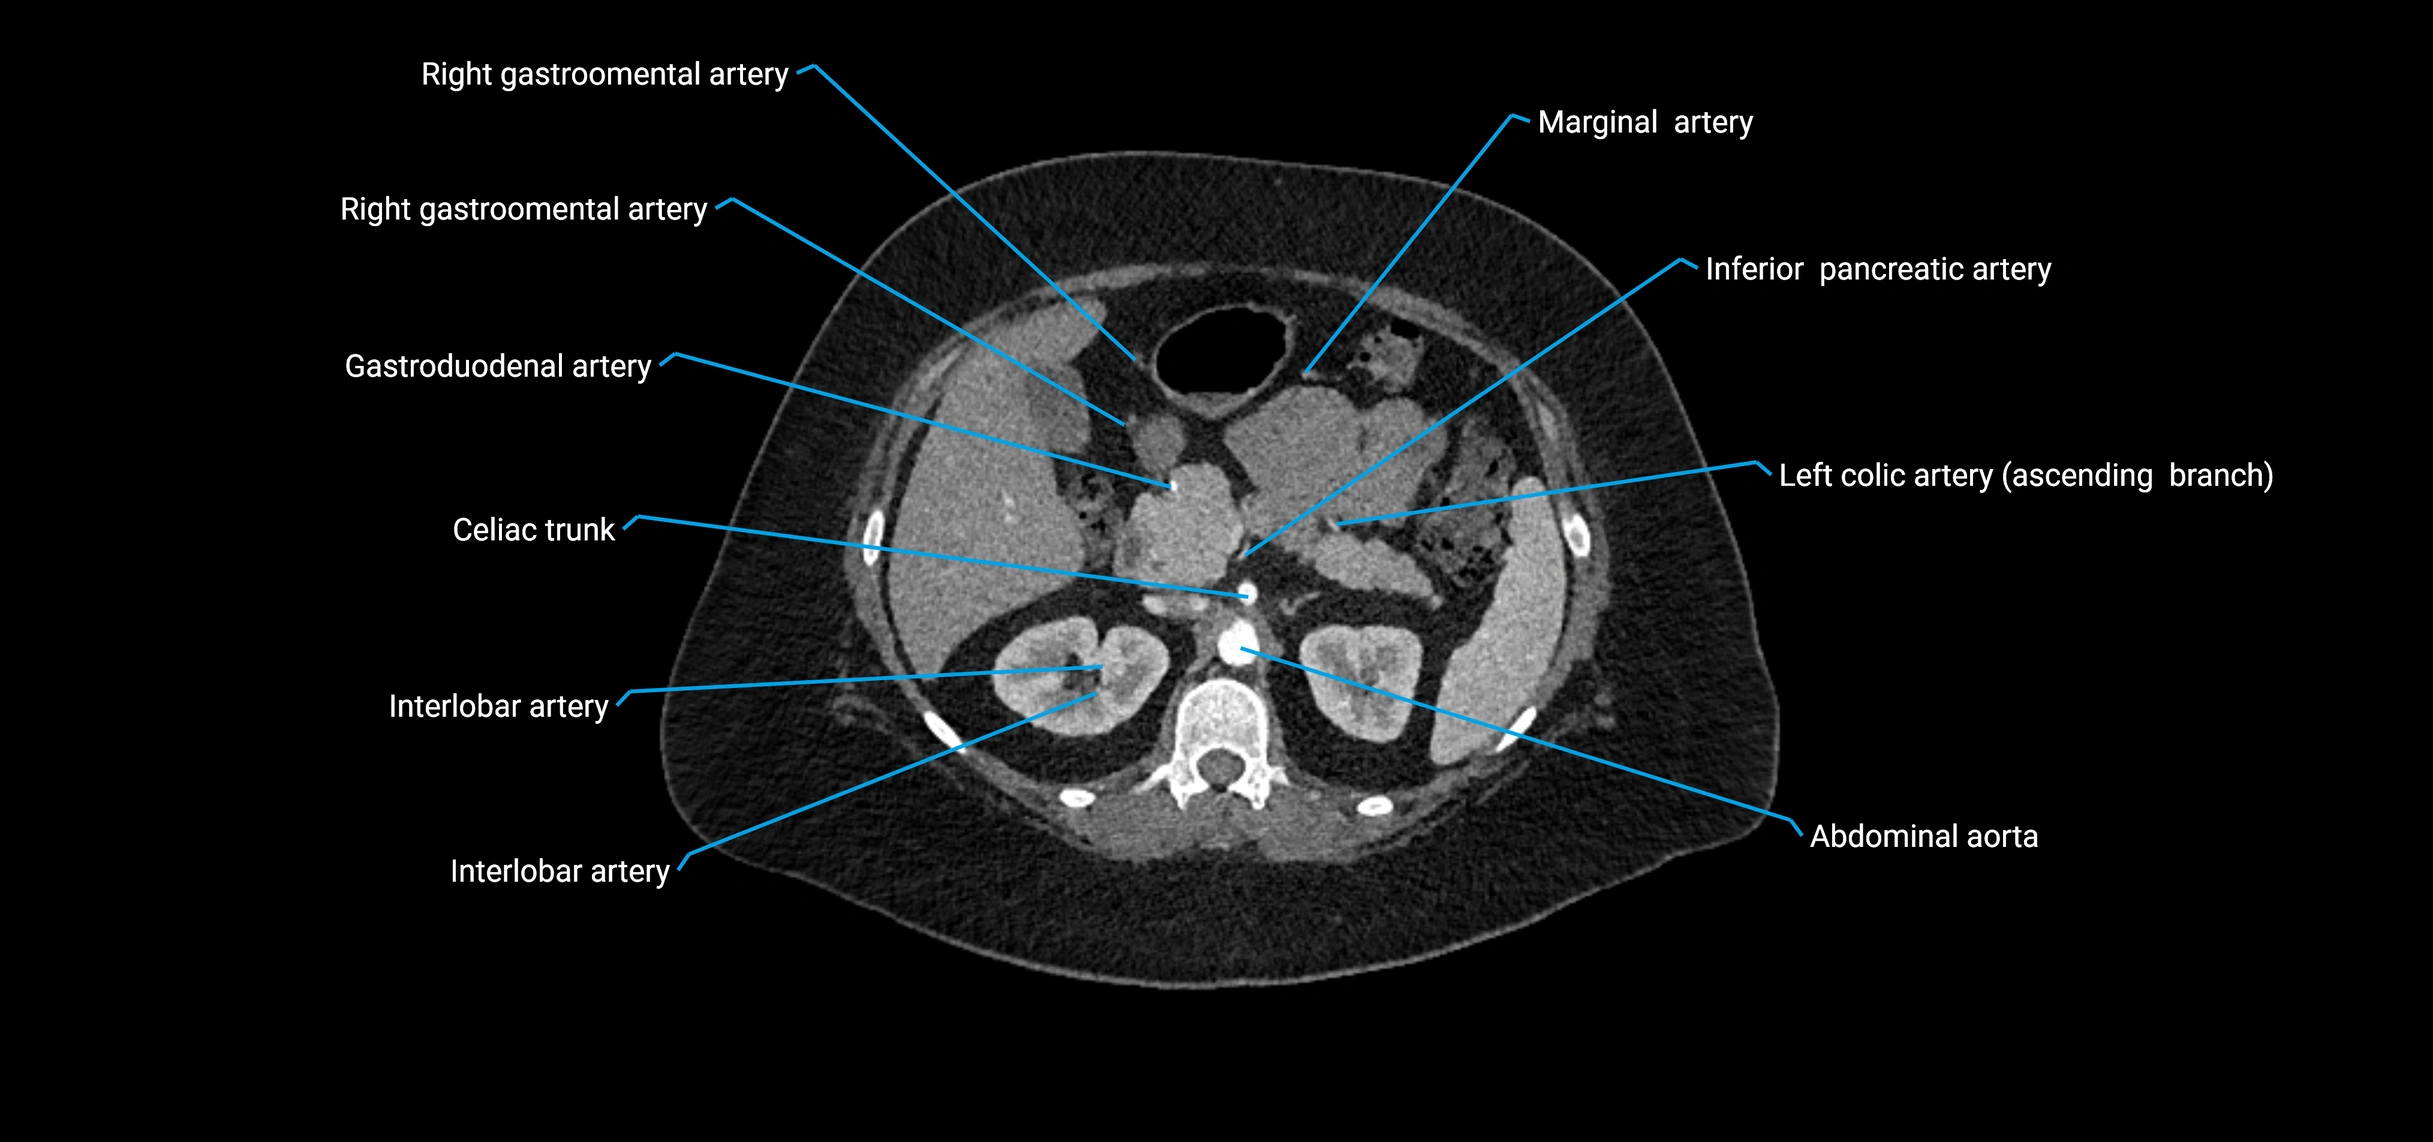

Contrast-enhanced CT (CTA):

• Gold standard for abdominal aortic imaging

• Provides excellent detail of lumen, wall, aneurysm, thrombus, and branch vessels

• Multiplanar and 3D reconstructions help in aneurysm measurement, stent graft planning, and dissection evaluation

• Detects acute rupture, traumatic injury, or occlusion with high sensitivity